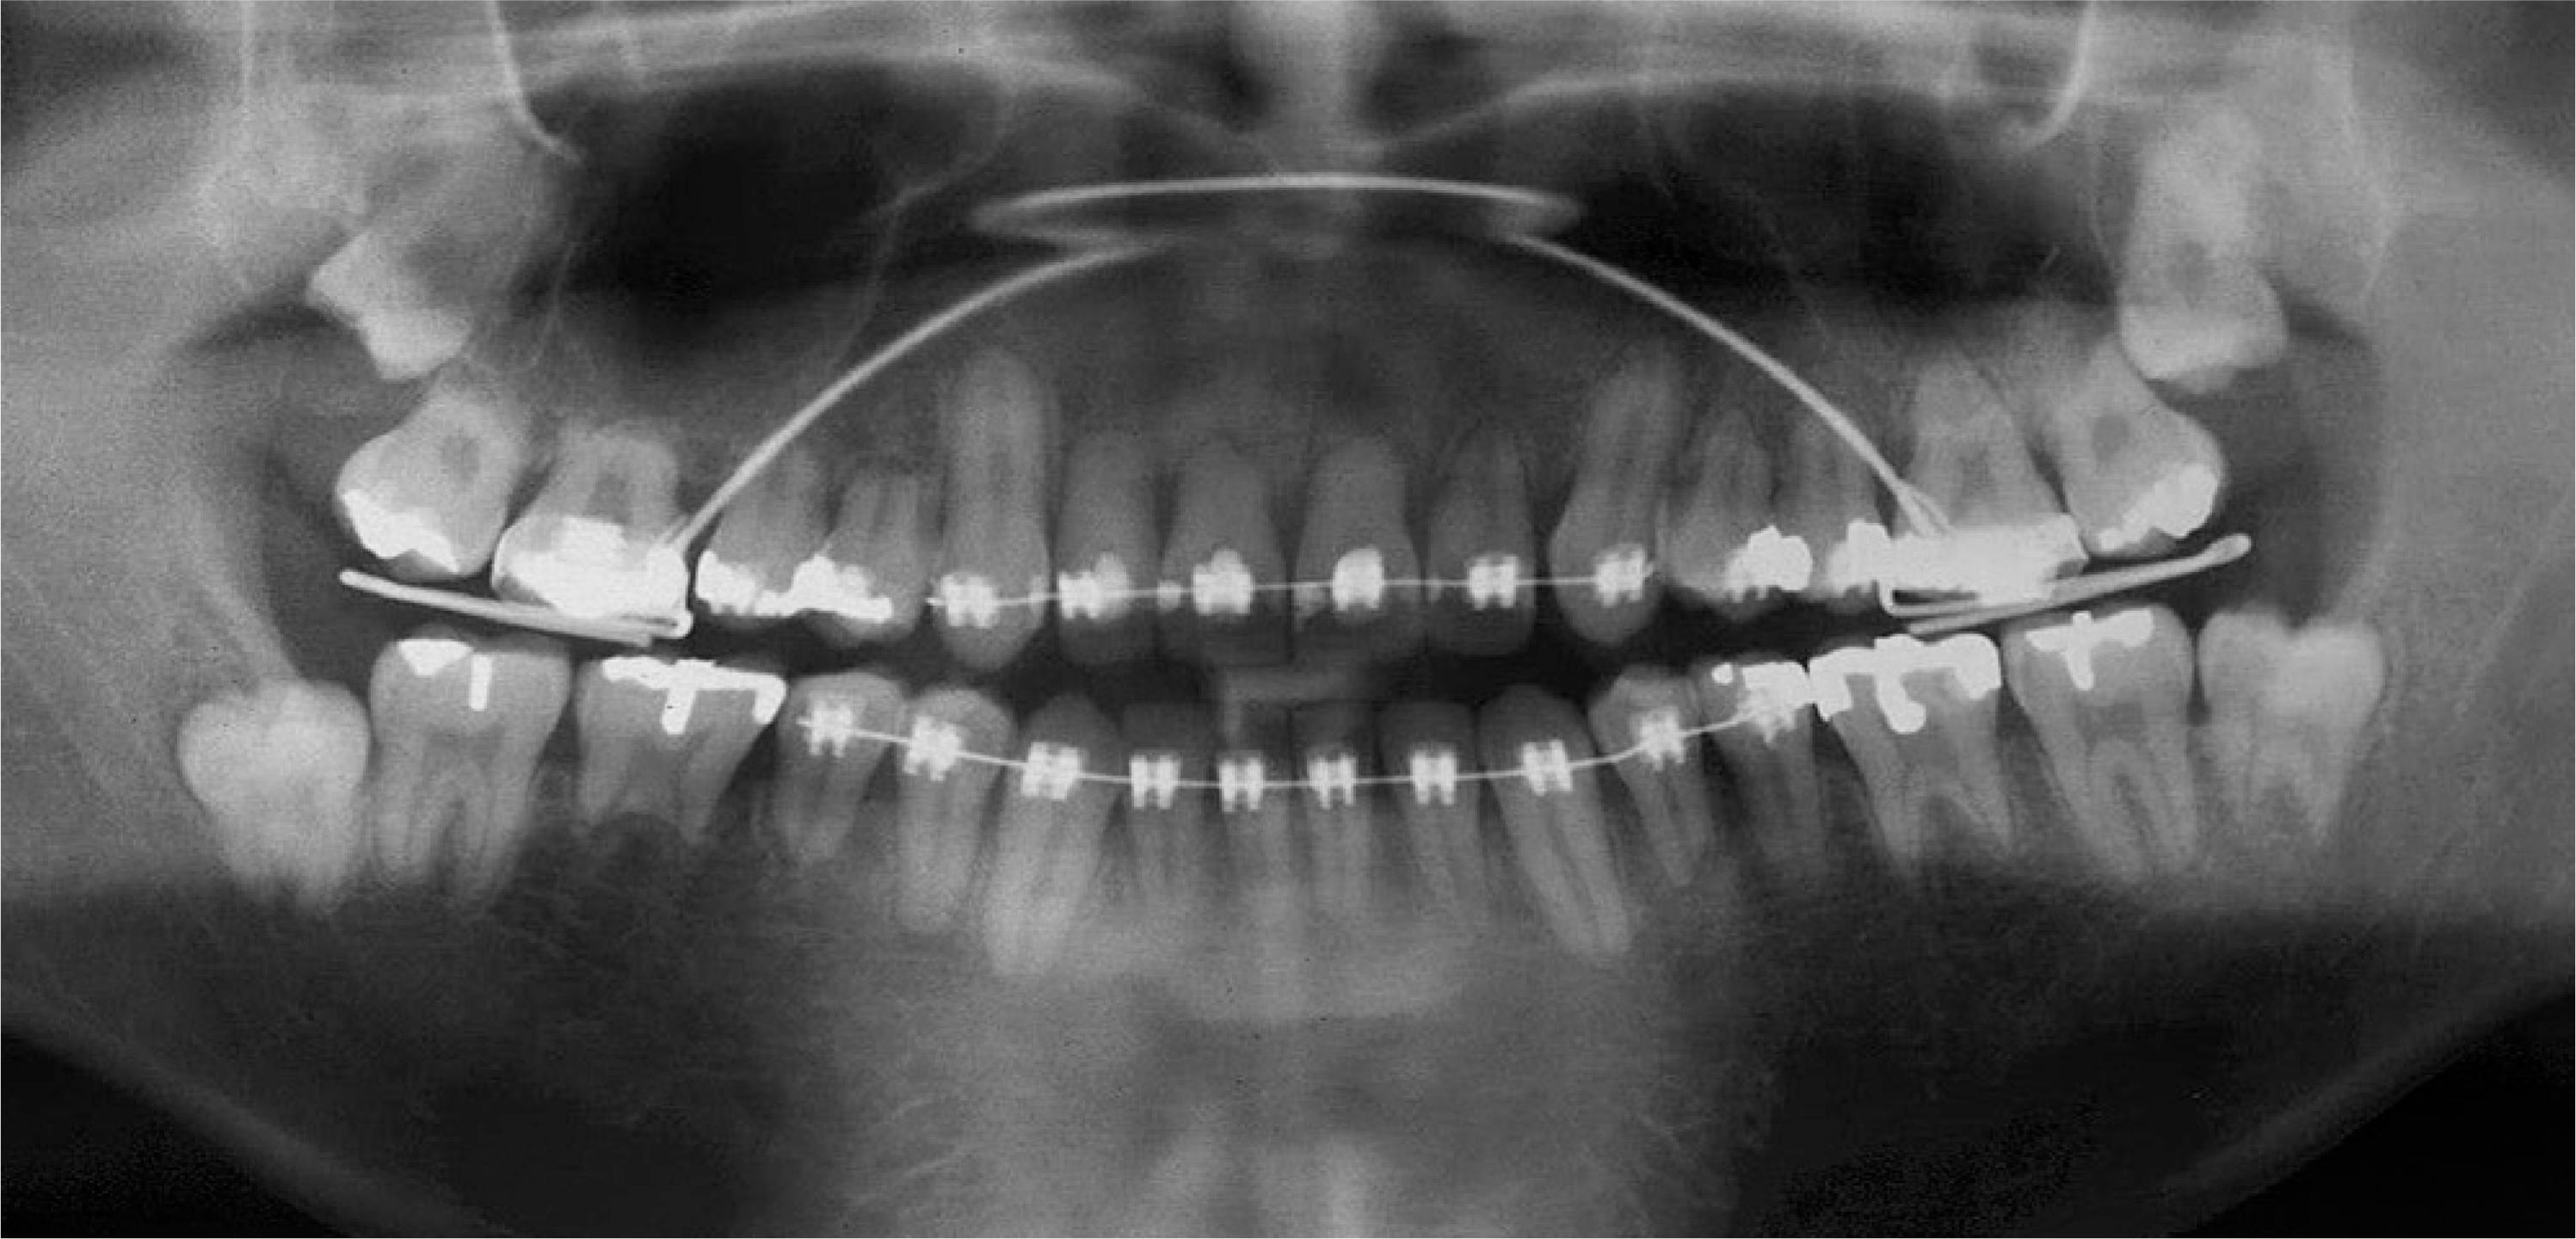

X-Matrix ứng dụng SmileStream trong việc phân tích phim và lên kế hoạch điều trị

Để khắc phục nhược điểm của công nghệ cũ, niềng răng X-Matrix ứng dụng các công nghệ hiện đại ngay từ bước thu thập dữ liệu để đảm bảo độ chính xác tuyệt đối:

- Chụp 3 loại phim: Cephalometric, Panorama và CT để khảo sát cấu trúc xương, tình trạng xương và các cấu trúc giải phẫu.

- Scan dấu răng bằng máy iTero Element 5D đại để khảo sát tương quan răng và mô mềm, xác định các sai lệch về răng và khớp cắn chính xác tới từng micromet.

Bác sĩ sẽ phân tích và lên kế hoạch điều trị cho khách hàng đảm bảo các tiêu chí chính xác, an toàn và không đau với sự hỗ trợ của các phần mềm kỹ thuật số hiện đại: